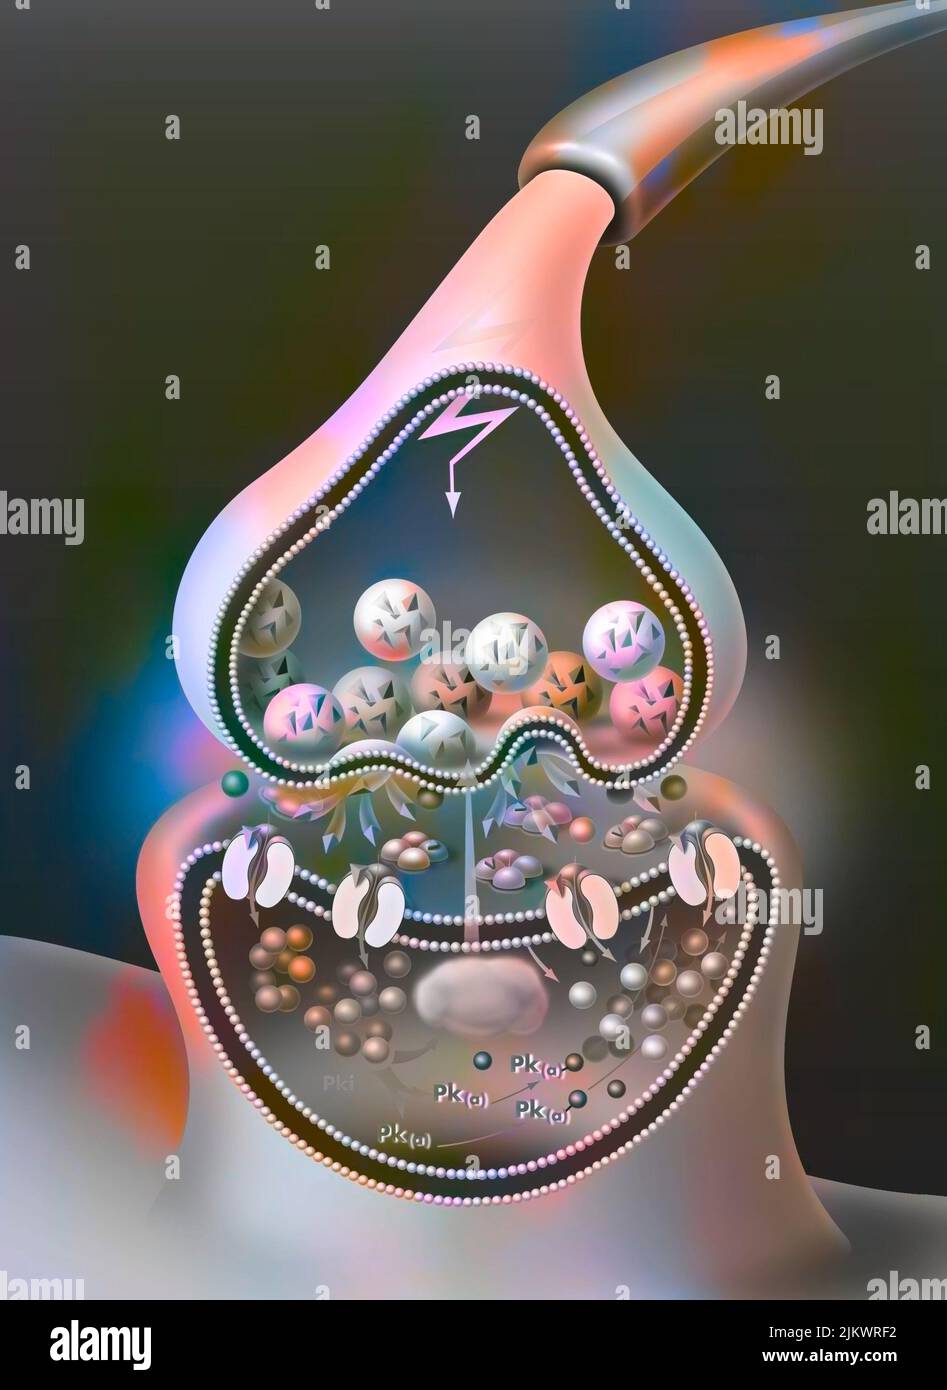

RF2JKWRF2–Pla (potentialisation à long terme) après une semaine, étape 2 : la synapse est stimulée avec une plus grande efficacité.